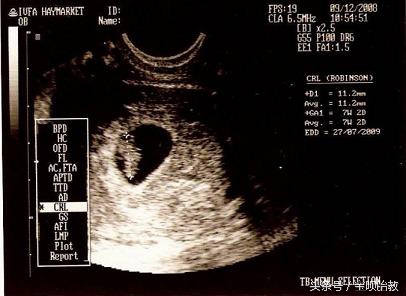

言归正传,看B超的胎囊就能够猜男女,那么胎囊到底是什么呢?

什么是胎囊?

胎囊,也叫孕囊,是怀孕最初胚胎的形态。

如何正确的胎囊看男女?

首先数据不能超过8周的,40多天是最合适的。

2、看形状:

像茄子或长条状的是男宝宝可能性大,圆圆的是女宝宝可能性大。

孕囊都是圆柱状的,每个B超师做B超的时候,截面会截取的方位不一样,有的横截面,有的截取竖截面,所以,看图片是长的还是圆的,不能判断男女。所以看数据的时候,数据一定要有3个。

3、看数据:

如果B超师取了40*20的截面,貌似男孩的数据,结果生出了闺女,就会造成孕囊看男女不准的说法。

所以这里一定要是3个数据。如果长和宽的相差在一倍以上男宝宝可能性大。长和宽相等女宝宝可能 性大。

如果孕囊成等差数列,比如40*30*20,这样就是女孩, 有3个数据最好判断,两个数据差不多,第三个数据比前两个小一倍,那肯定是儿子,如果成递减数据就是女儿。